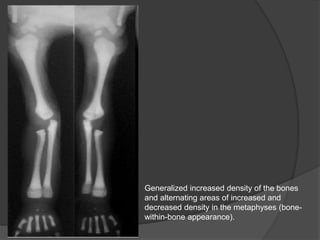

Generalized increased density of the bones

and alternating areas of increased and

decreased density in the metaphyses (bone-

within-bone appearance).

Generalized increased densityof the bones and alternating areas of increased and decreased density in the metaphyses (bone- within-bone appearance).